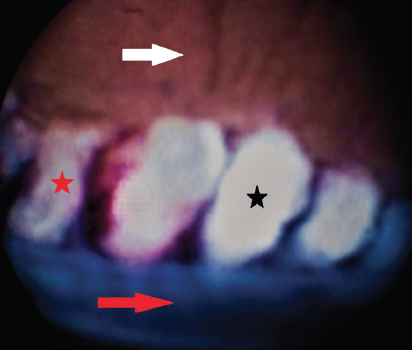

The probe is inserted through the incision (Figure 2), and the surgeon views the procedure on a monitor and begins to apply laser to the ciliary processes. The energy is slowly increased until shrinkage and whitening of the ciliary processes can be seen (Figure 3).11

Figure 3. View of ciliary processes on the endoscopy unit monitor showing untreated ciliary process (red star), treated ciliary process with whitening (black star), posterior iris surface (white arrow), and anterior surface of lens capsule (red arrow).